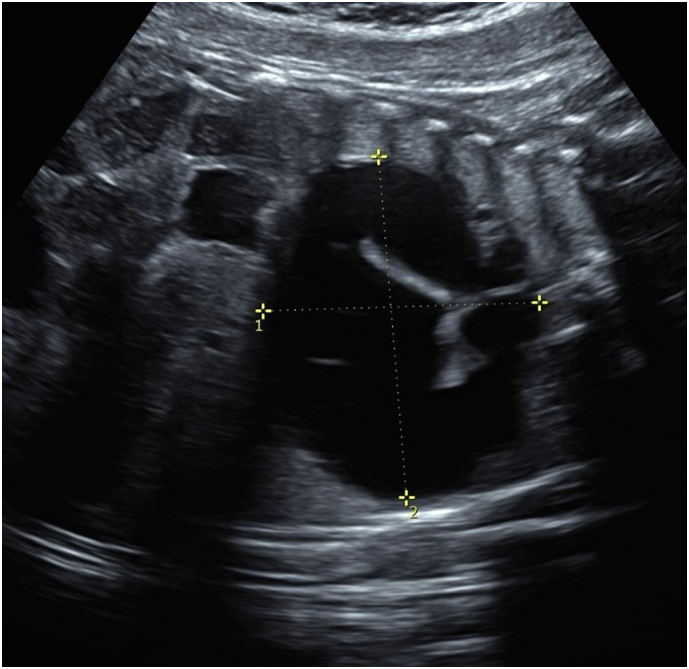

A 29-year-old woman, gravida 3 para 2, was referred to a fetal diagnosis center at 21 weeks of gestation for evaluation of a fetal cystic chest mass. The patient's medical history and family history were noncontributory. Ultrasound revealed a cystic mass in the right thorax measuring 1.9 × 2.1 × 2.6 cm. (Fig. 1), presumed to be a right congenital pulmonary airway malformation (CPAM). The spine images were limited but one area of the cervical thoracic spine on ultrasound was suspicious for dysraphism (Fig. 2). Fetal echocardiogram was normal and no other anomalies were identified.

Fig. 1.

Prenatal ultrasound demonstrated a right-sided chest mass measuring 1.9 × 2.1 × 2.6 cm with leftward shift of the heart due to mass effect.